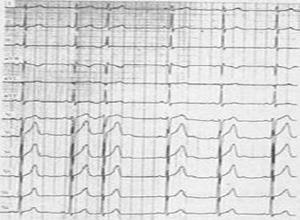

简介房性期前收缩即房性过早搏动(atrial premature beats,APB),又称房性早搏、房早,房性期前收缩,起源于窦房结以外心房的任何部位。正常成人进行24小时心电检测,大约60%有房性期前收缩发生。各种器质性心脏病患者均可发生房性期前收缩,并经常是快速性房性心律失常出现的先兆。